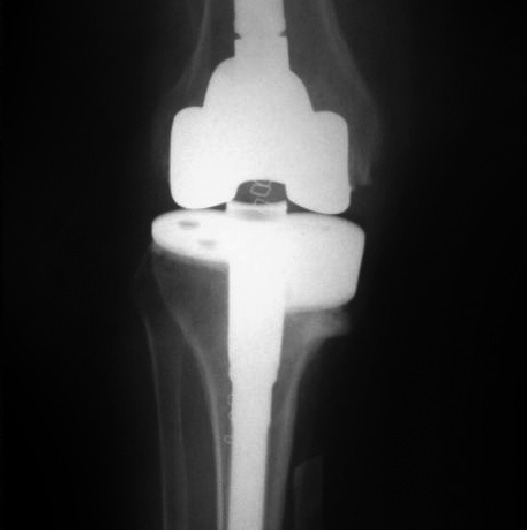

PRÓTESIS DE REVISIÓn